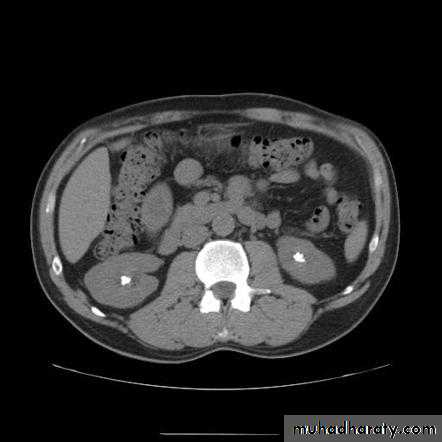

Nephrocalcinosis

Deposition of calcium salts in the medulla or cortex of the kidney.Medullary Nephrocalcinosis